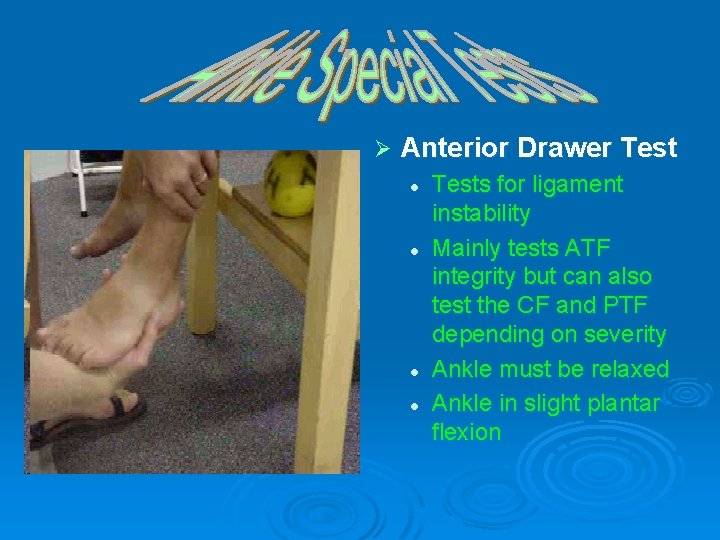

Ø Anterior Drawer Test l l Tests for ligament instability Mainly tests ATF integrity but can also test the CF and PTF depending on severity Ankle must be relaxed Ankle in slight plantar flexion